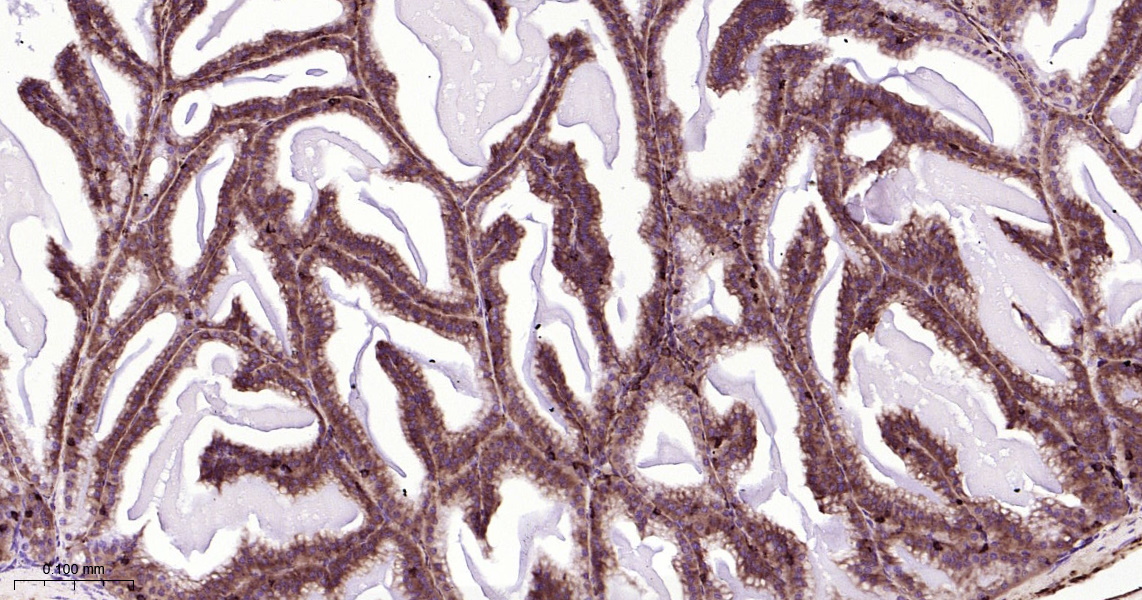

• IHC-P

IHC-P IHC-P1:100-500